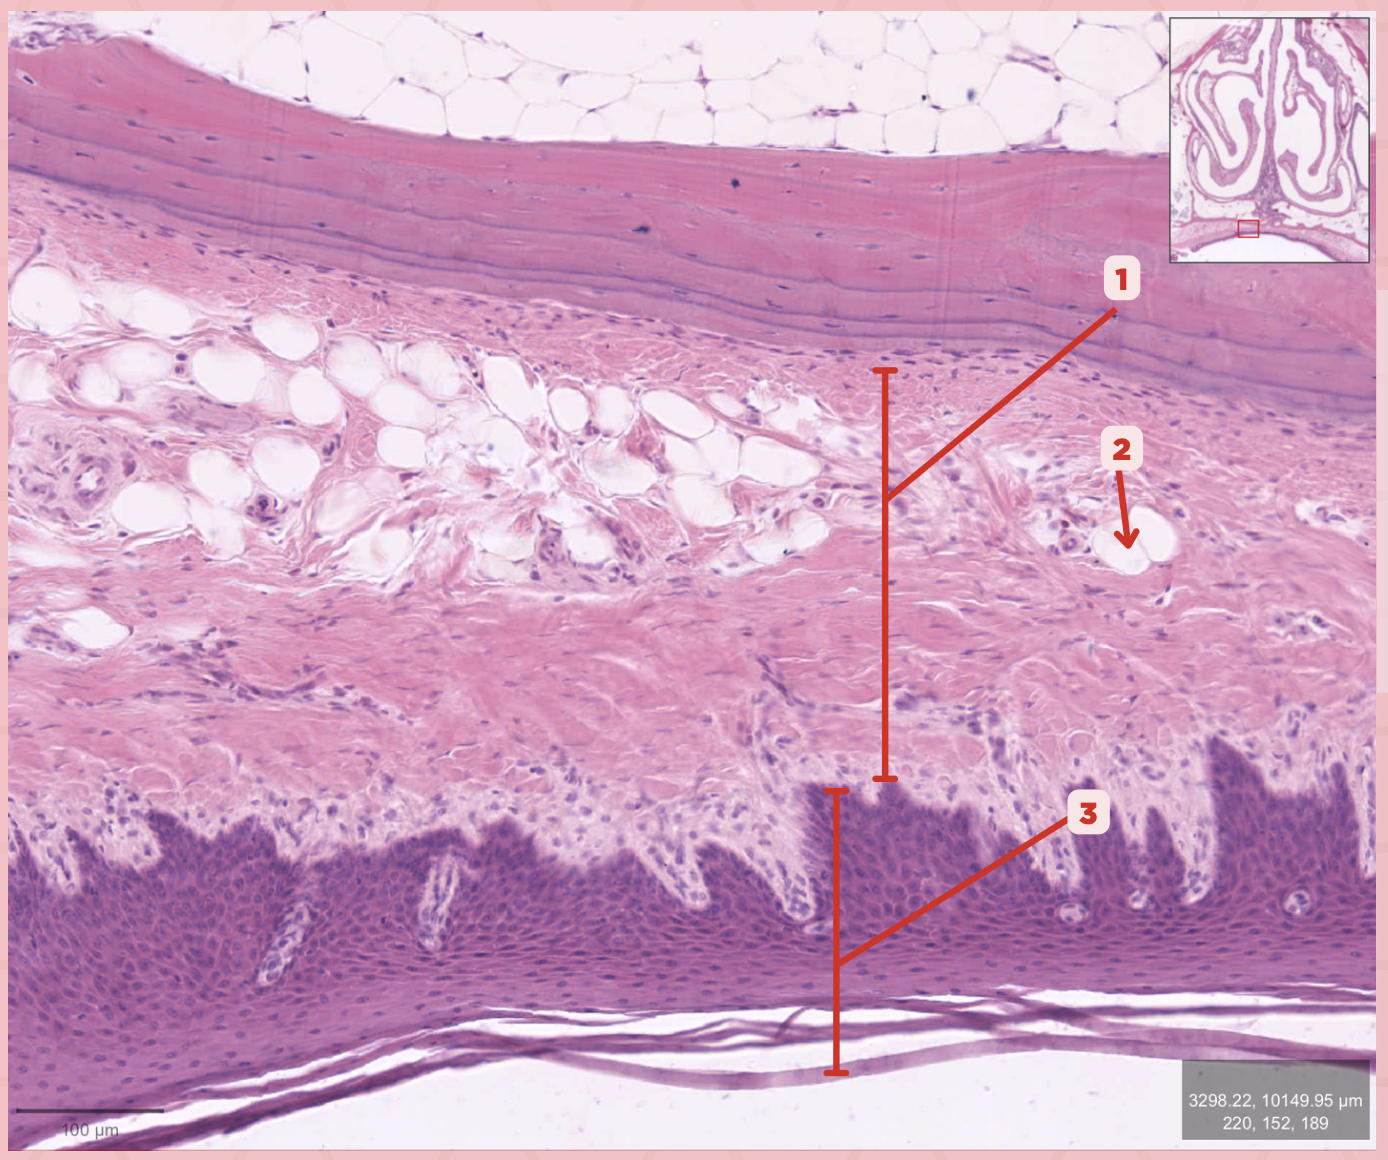

Lamina Propria

Identify the structure labeled as 1.

Adipocytes

Identify the structure labeled as 2.

Keratinized stratified squamous epithelium

Identify the structure labeled as 3.